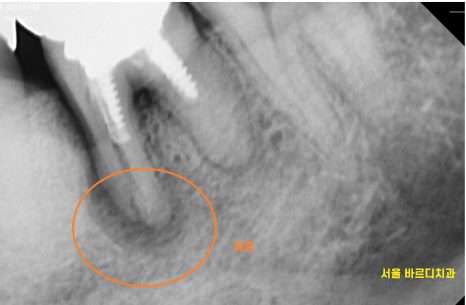

그 상태에서 자꾸 씹다보니

뿌리 주변 뼈가 녹아서

까맣게 보이네요~

23.10.17